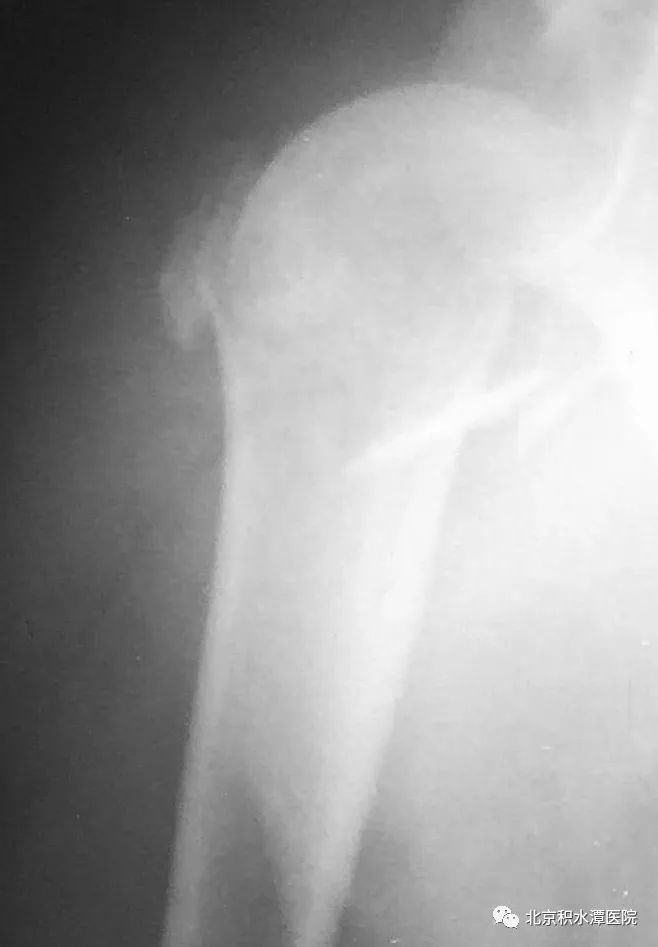

2007年,患者是甘肃一名37岁的青壮年男性,因外伤致肱骨近端骨折,在当地手术内固定治疗。术后很不幸地出现了内固定失效。此后,该患者经历了内固定失效后全肩关节置换、感染后扩创、肩胛盂骨性重建、APC手术,15年多次手术这样一个复杂痛苦的历程。

2009年,因骨折不愈合、内固定失效,患者在当地行全肩关节置换术,术后10天出现伤口愈合欠佳,渗液较多,经换药、抗炎治疗好转后出院。后反复出现伤口窦道形成,都经换药后愈合,但肩关节功能欠佳。